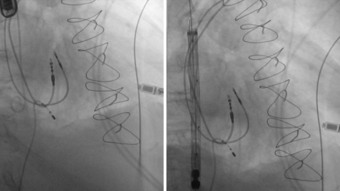

Pdf Transcatheter Mitral Valve Chord Repair

Transcatheter Mitral Valve Chord Repair Savic Annals Of Cardiothoracic Surgery